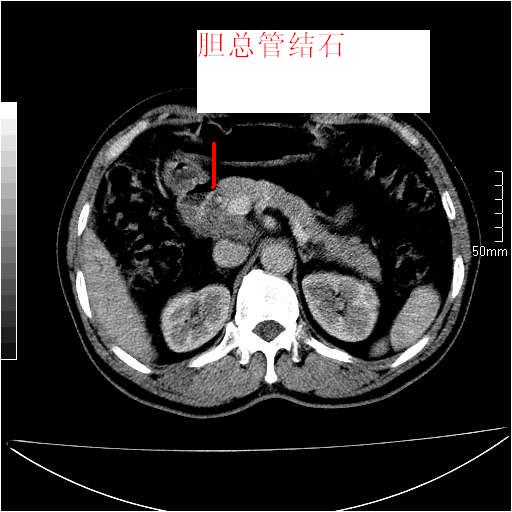

男性,54岁,皮肤黄染,搔痒一周余.b超示肝左叶回声异常.初步诊断1胆总管下段结石2胆囊结石伴慢性胆囊炎请各位战友帮忙看一下肝脏多发低密度如何解释恰当.增强效果不是很好.请大家见谅.

1、胆总管及肝内胆管扩张,(由于片子质量问题,不太好观察)。2胆囊癌?

首先,胆总管下端结石梗阻伴肝内胆管扩张可确定。